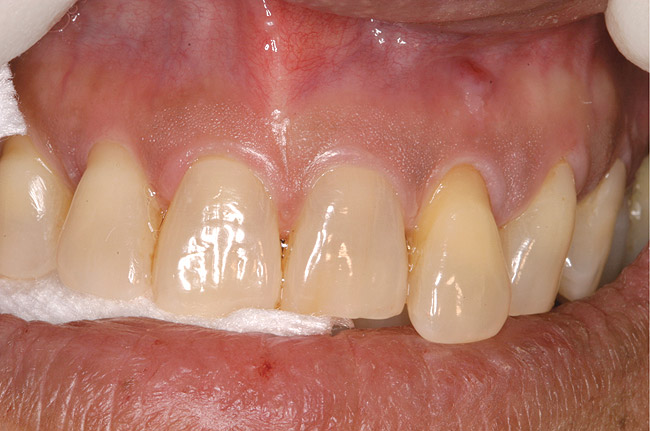

Figure 10  Implants seen in Figure 9 restored approximately 3 months after placement.

Figure 10